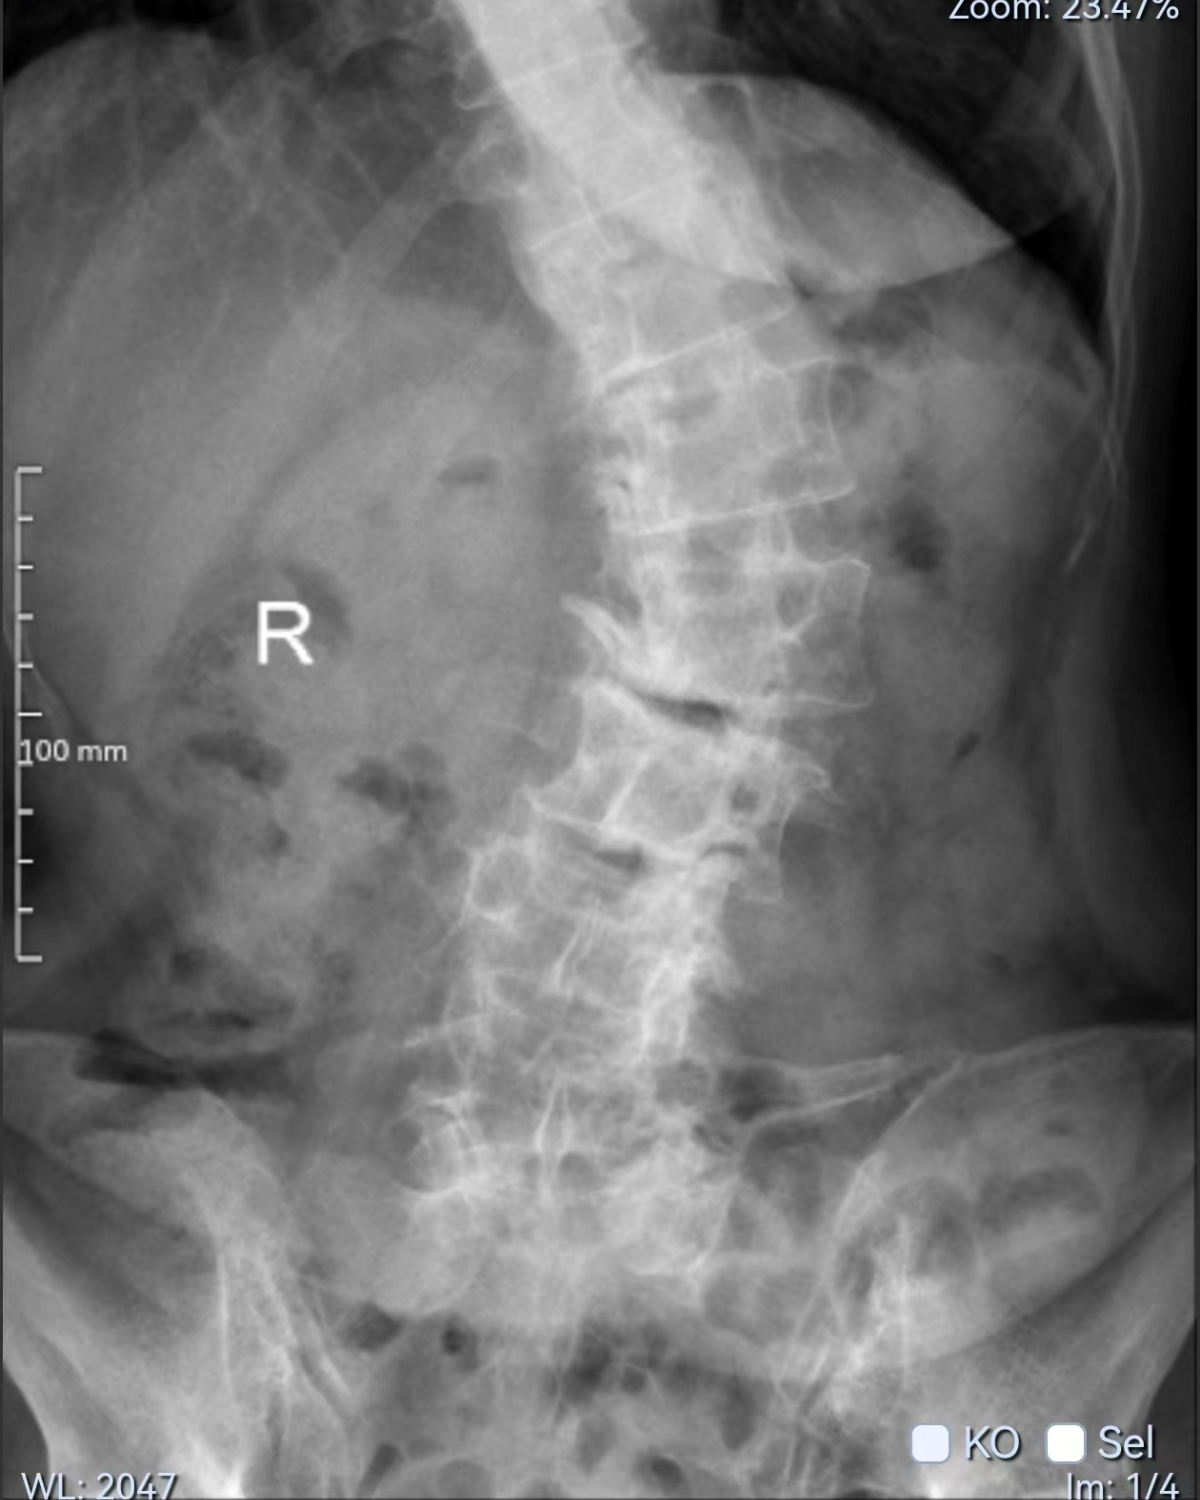

桑大姐今年60多岁,因为常年劳作导致腰部长期疼痛并逐渐变形,近半年疼痛严重,基本不能坐站,靠卧床休息。同时,桑大姐还有糖尿病、肾功能不全,贫血,营养不良等疾病,长期卧床导致出现了下肢血栓,在外院住院治疗10多天不见好转,仍然不能下床活动。省级医院的建议是进行手术治疗,但桑大姐因家庭原因,无法实现去省级医院治疗。后多方打听,寿光和信医院骨外科脊柱手术做得不错,便前来就诊咨询。

骨外科李刚主任总体评估后,发现病人体弱多病,对于进行纠正侧弯及减压融合这个大手术来说确实风险极高,但是不做手术,病人就很难再从床上起来生活了。

因为常年脊柱侧弯并旋转畸形,周围增生异常严重,正常的解剖结构无法辨别,完全靠经验来完成操作。手术过程异常艰难,但病人的信任是所有参与人员全力以赴的动力。历经7个多小时手术,弯曲的脊柱变直了,狭窄的腰椎椎管和受压的神经根得到了充分的减压。